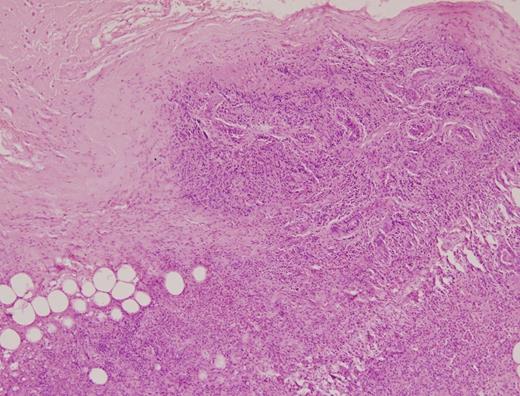

In view of the fact that Triple assessment of the breast lump was not conclusive either for carcinoma or ruling it out all together, open biopsy was undertaken. Biopsy revealed diffuse and dense periductal and stromal inflammatory infiltrate comprising sheets of plasma cells, large number of eosinophils, scattered foamy histiocytes and some lymphocytes. There was diffuse stromal fibrosis and no cells suggestive of malignancy were seen. The diagnosis of eosinophilic mastitis was suggested.